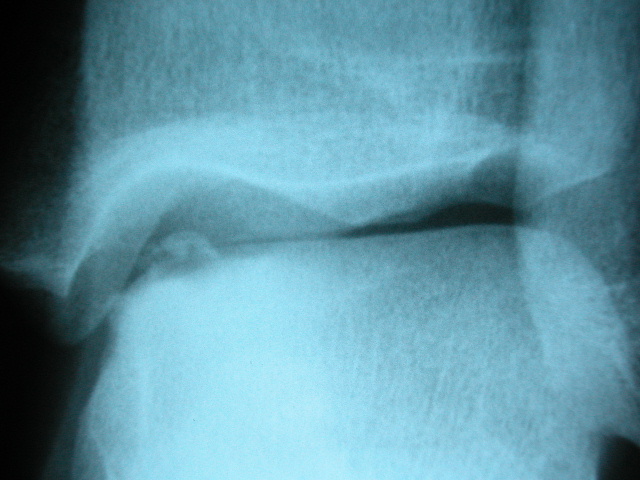

Fractura supracondílea de codo.

Fractura supracondílea de codo.Tras reducción y osteosíntesis.

Fractura supracondílea de codo. Tratamiento con agujas.